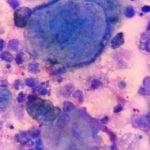

I risultati della ricerca suggeriscono che il nuovo farmaco potrebbe essere altamente efficace contro il glioblastoma, uno del tipi più devastanti e più comuni di tumore al cervello negli adulti.

I ricercatori hanno testato il nuovo farmaco sulle cellule tumorali prelevate dal tessuto di adulti e bambini con il cancro al cervello. Essi hanno scoperto che sia singolarmente, sia in combinazione, gli ingredienti presenti nel nuovo farmaco erano dieci volte più efficaci per uccidere le cellule tumorali di qualsiasi combinazione di altri farmaci attualmente utilizzati.